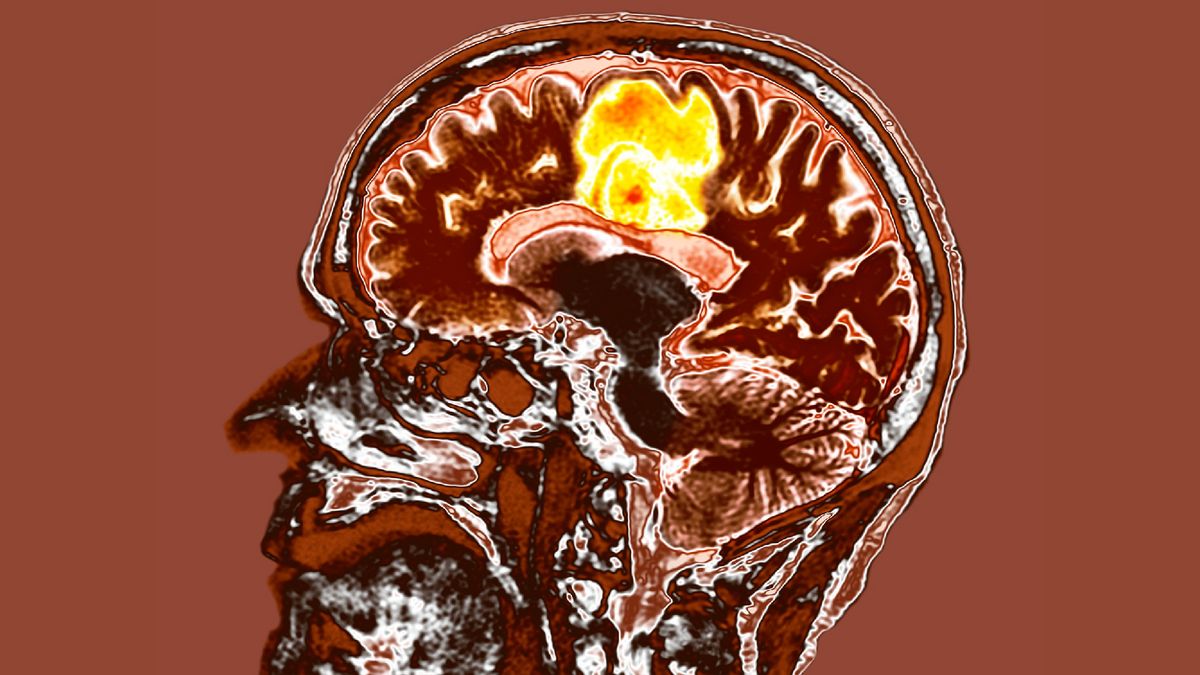

Habituellement, les tumeurs des patients sont cartographiées par IRM avant que les patients ne subissent une radiothérapie. Dans le nouvel essai, les chercheurs ont ajouté un autre type d’imagerie, appelé 18F-DOPA PET. Il s’agit d’une sorte de tomographie par émission de positons (TEP), une technique dans laquelle les médecins injectent une petite quantité de traceur radioactif au patient et l’analyse identifie ensuite où va la majeure partie de ce traceur. Cela permet de détecter des zones de métabolisme inhabituel, notamment les cellules cancéreuses, qui sont plus occupées métaboliquement que les cellules saines. Le 18F-DOPA PET utilise un traceur radioactif particulièrement efficace pour détecter les anomalies dans certains neurones.

Après les scintigraphies cérébrales, les chercheurs ont ciblé les régions cancéreuses actives avec un type de rayonnement appelé thérapie par faisceau de protons. La radiothérapie protonique utilise des particules lourdes chargées pour faire le travail, plutôt que les rayons X utilisés dans photon radiation.